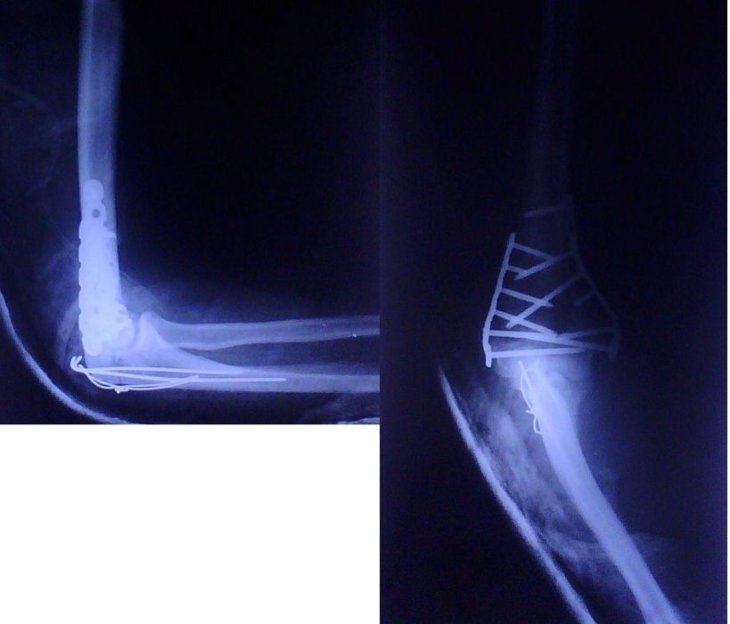

To museli odříznout olecranom při operaci, aby to mohli dát dokupy – tak to je fakt smůla :-( Vcelku zajímavé porovnání kvality těch dvou posledních snímků, co tu jsou. Jako rentgenologg byc chtěl rozhodně pracovat v té předcházající nemocnici.

Lister:ulna zlomená nebyla,ta se musela naříznout až po otevření

byla to otevrena zlomenina takze zazitek no… cca 400m jsem s tou rukou sel sam, mel jsem to jen lehce v dlaze pak jeep pak sanitka… zachranari byli radi ze me od tama nemuseli nest…

Tak to je slušná práce. Tos musel mít ten konec pažní kosti slušně roztřískaný, že museli udělat tohle. Navíc i zlomená ulna, to je fakt smůla :-(

tak co se stalo? spadl jsem na kole :) tohle je ale \„pohoda\“ problem vidim v nervech ty jsou v hajzlu zatim no :(